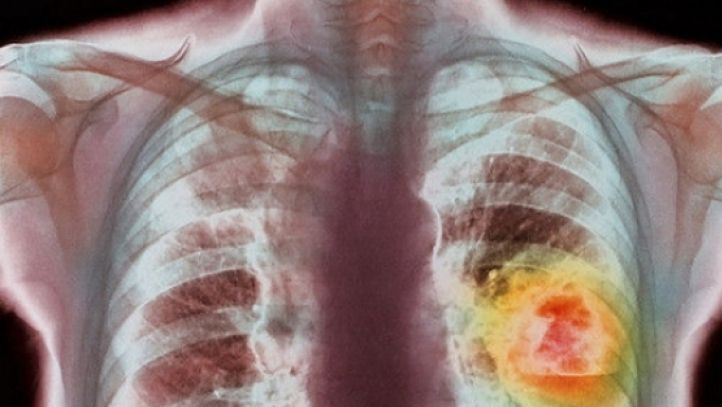

Ai aceste simptome? Ar putea fi cancer pulmonar

Potrivit ultimelor studii, peste 90% din cazurile de cancer la plamani apar in cazul persoanelor care fumeaza. Cu toate acestea si nefumatorii pot fi afectati de aceasta boala, daca stau mult timp in fum de tigara. Din pacate, simptomele cancerului pulmonar apar de cele mai multe ori atunci cand boala este intr-un stadiu avansat si este deja extinsa si spre alte organe.

Cancer la plamani. Simptome

– Lipsa apetitului alimentar este una dintre cele mai intalnite simptome in cazul cancerului la plamani. Pierderea rapida in greutate si lipsa senzatiei de foame trebuie sa traga un semnal de alarma si e necesara o vizita la medic

– Greutatea in a respira, senzatia ca ramai fara aer si presiunea din piept simtita permanent poate sa fie un alt simptom al cancerului pulmonar.

– Oboseala cronica este un alt simptom al cancerului pulmonar, avand in vedere ca plamanii nu mai functioneaza corespunzator si astfel organismul nu mai este oxigenat asa cum trebuie. Mai mult decat atat, oboseala este o urmare a lipsei poftei de foame care duce la o proasta alimentare a organismului.

– Tusea persistenta care nu dispare mai bine de 3 saptamani si se intensifica trebuie sa traga neaparat un semnal de alarma, fiind unul dintre cele mai intalnite simptome ale cancerului la plamani. Tusea in cazul cancerului este insotita de dureri in piept si in acest caz este imperativa o vizita la medic.